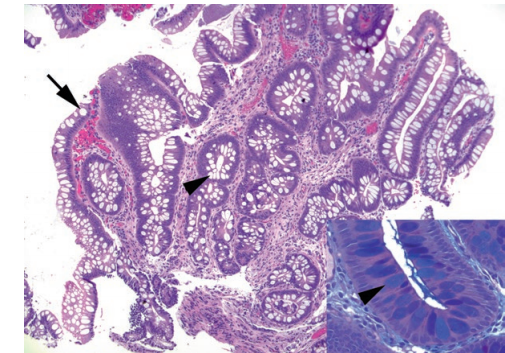

Goblet cells in Barrett’s esophagus. The presence of columnar epithelium with goblet cells indicates Barrett’s esophagus. Goblet cells are round cells that appear clear on H&E stain and are typically flanked by the purplish absorptive-type cells. Back-to-back mucinous cells resembling a row of teeth are more likely to be gastric foveolar epithelium. Goblet cells may be present at the surface (arrow) or in deep glands (arrowhead). Inset: A PAS/AB stain confirms the goblet cells, which stain indigo blue (arrowhead).